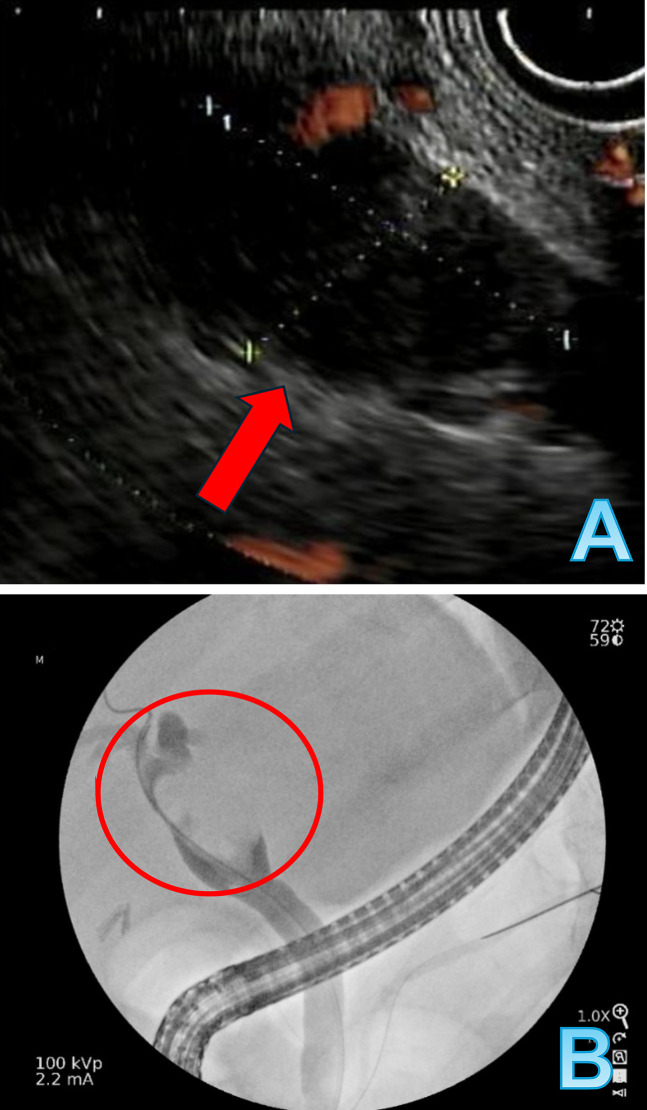

胆管癌是一种罕见的胃肠道恶性肿瘤,年发病率为每10万人0.3 - 6例,通常约95%的病例报告为腺癌。它可以是遗传易感性和各种危险因素共同作用的结果,如但不限于胆总管囊肿、胆石症/胆总管结石,但由于难以获得诊断组织,其诊断具有挑战性。在这项研究中,我们提出了一个具有挑战性的诊断病例,揭示了胆管门周区域未分化的破骨细胞样巨细胞癌。

Cholangiocarcinoma is a rare gastrointestinal malignancy with an annual incidence of 0.3 to 6 cases per 100,000, and, usually, it is reported as adenocarcinoma in about 95% of the cases. It can develop as a result of combination of genetic predispositions and various risk factors like but not limited to choledochal cysts, cholelithiasis/choledocholithiasis, yet its diagnosis is challenging due to difficulties in obtaining tissue for diagnosis. In this study, we present a challenging case in diagnosis that reveals undifferentiated carcinoma with osteoclast-like giant cells in the perihilar region of the bile duct.